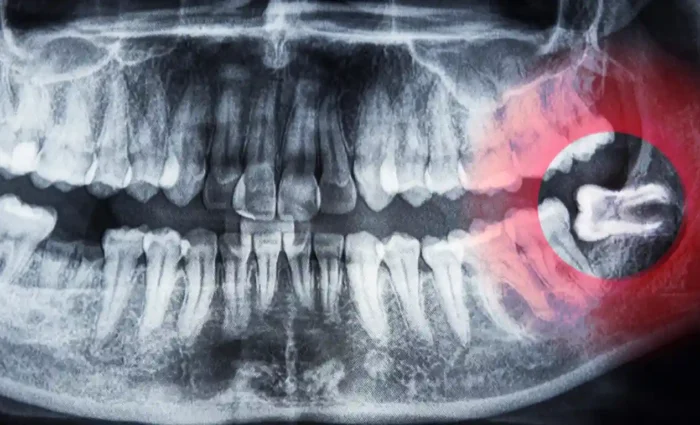

Medically Reviewed By Dr. Mert Albayrak, DDS Oral and Maxillofacial Surgeon Most dentists removed wisdom teeth as a preventive strategy for years. Early removal was thought to minimise congestion and infection. As dental science advances, specialists are questioning this standard practice. More specialists are arguing for a conservative approach, indicating that not everyone needs wisdom […]